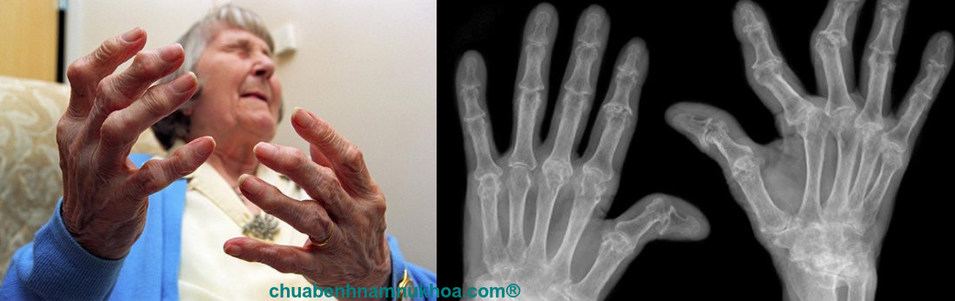

Định nghĩa: Viêm đa khớp dạng thấp được đặc trưng bởi các biểu hiện ở các khớp đối xứng hai bên. Các hình ảnh bào mòn khớp trên X- quang, xét nghiệm về yếu tố thấp dương tính, và về mặt bệnh học. Có tình trạng viêm màng hoạt dịch tăng sinh mạn tính với sự tăng sinh nhung mao, thâm nhiễm các tế bào lympho và tương bào và các hạch. Đây là một vì vậy ít nhiều phù hợp với cái tên “bệnh lý dạng thấp”. Tình trạng bệnh lý này bao hàm trong các bệnh mô liên kết hệ thống. Tiêu chuẩn chẩn đoán đã được đưa ra thống nhất.

Bàn tay: Khởi phát điển hình là sự xuất hiện đau, cứng khớp, sưng và nhạy cảm đu ở các khớp liên đốt gần và khớp đốt bàn ngón tay. Sưng nề dạng “hình thoi” của các khớp liên đốt gần làm cho các ngón tay có dạng hình thoi, dạng con suốt đặc trưng và các đầu khớp của các khớp liên đốt gần, khớp đốt bàn ngón tay bị sậm màu.

Bệnh lý mắt: Người ta cũng ghi nhận một số biểu hiện ở mắt trong loại bệnh lý viêm khớp này. Thường gặp nhất là viêm thượng củng mạc. Loại này thường không triệu chứng. Kế đến là thường gặp viêm củng mạc. Biến chứng nặng nhất ở mắt là thủng do nhuyễn củng mạc. Biến chứng này gây ra mù tạm thời hoặc vĩnh viễn. Các biểu hiện hệ thống: Loét da thường ở vùng xương cùng cụt hoặc ở cẳng chân là do viêm các động mạch lớn. Một triệu chứng cũng có thể thấy là ban đỏ lòng bàn tay và nó quan trọng để tạm không nghĩ đến bện gan từ triệu chứng này trên một bệnh nhân bệnh viêm đa khớp dạng thấp. Một số triệu chứng hệ thống khác được đề cập trong các hội chứng có liên quan. Giai đoạn sớm: Có hình ảnh loãng xương và hình ảnh bào mòn đoạn cạnh khớp. Giai đoạn muộn: Mất khe khớp, có sự hủy xương và sai lệch khớp.